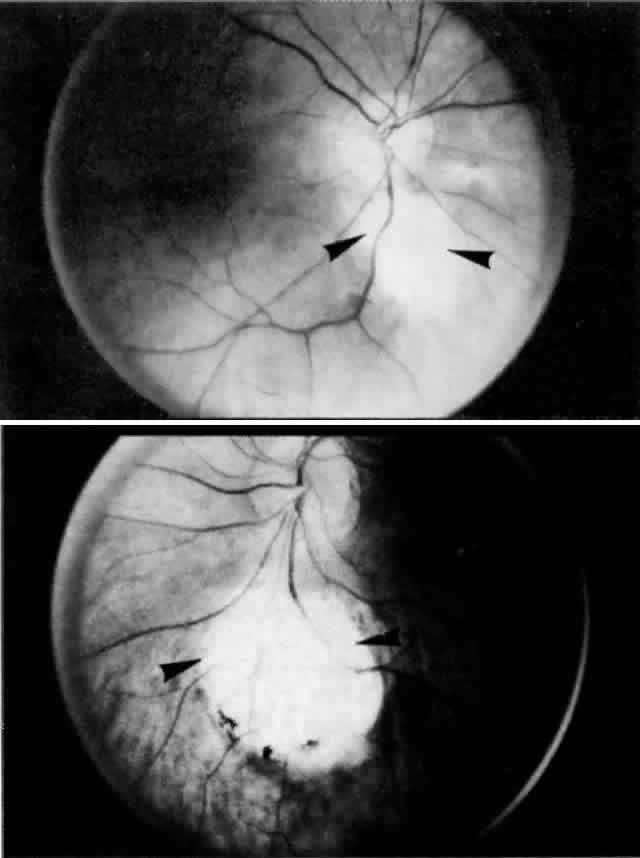

Heimann,6 however, was able to identify arteries as two-layered, narrow vessels and veins as tubes with wide lumina and a single layer of endothelium by the end of the second month. At first, the endothelium-lined tubes are concentrated inferiorly and distally. With invagination of the optic vesicle, pigment appears in the outer layer of the optic cup. Melanin first appears in the RPE between gestational weeks 5 and 7.1,2,4,7 Pigmentation is linked to capillary formation, as primitive capillaries develop from the plexus external to the pigmented areas. The subjacent choroid and sclera never form correctly if the RPE fails to develop, as happens in colobomas (Fig. 7).

Fig. 7. Asymmetric colobomas (arrowheads) of posterior pole in right (above) and left (below) eyes of same patient. Failure of closure of embryonic fissure results in typical defects in retina and uvea inferonasal to the optic disc.